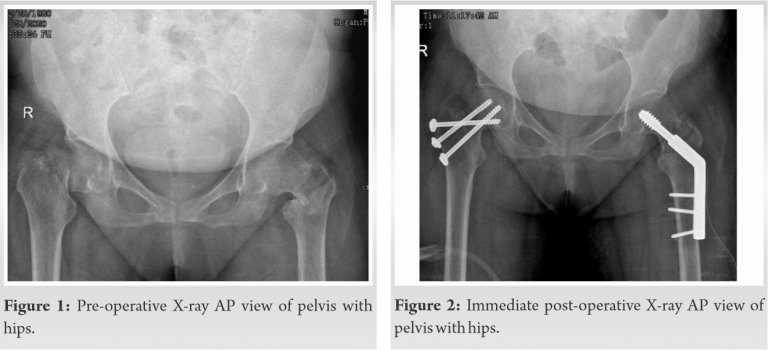

Her medical history revealed chronic kidney disease Stage IV and hypertension for which she was taking medication. Patient was examined for any other injury which may get masked because of these severe painful conditions. Radiological investigation revealed fracture neck of femur on right and intertrochanteric fracture on the left side (Fig. 1) and undisplaced fracture of lateral border of right scapula. Both lower limbs were immobilized with bilateral skin traction and for scapula fracture universal shoulder immobilizer was used. On investigation, she was found to be anemic with hemoglobin 5.7 gm/dl, her serum creatinine level was 4.83 mg/dl, and serum potassium was 2.8 meq/l. General physician, nephrologist, and anaesthesiologist were involved to optimize the medical condition of the patient as she needed major surgery. She was an active lady and our goal was to bring her to pre-injury level as early as possible. Dynamic hip screw fixation has stood the test of time for fixation of stable intertrochanteric fracture. In elderly patient, a prosthetic replacement is adequate for fracture neck of femur but at the age of 41 years it was reasonable to plan preserving the femoral head. The presence of this combination of injury in a comorbid patient and trying to preserve the femoral head presented an additional challenge in attempted osteosynthesis.

We planned dynamic hip screw for the intertrochanteric fracture and multiple cannulated cancellous screws to stabilize fracture neck of femur in the same sitting. The patient and relatives were prognosticated about the per-operative, post-operative, early, and late complications. In the operation theater with the patient on traction table, we first stabilized the intertrochanteric fracture with dynamic hip screw on the left side. After attempting closed reduction of the displaced femoral neck fracture on the right side, under image intensification, and having achieved it, it was fixed with three 6.5 mm cannulated cancellous screws, one of them as derotation screw. The per-operative period was uneventful. For next 48 h, she was kept in high dependency unit for monitoring after which she was shifted to the general orthopedic ward. Check X-ray taken on 2nd post-operative day was acceptable (Fig. 2, 3, 4). The same day 1st change of dressing was done. In bed physiotherapy was started with leg hanging and quadriceps exercise. Right shoulder remained immobilized. Patient was discharged with advice to attend OPD for stitch removal on 14th post-operative day. At stitch removal, her surgical wounds were found to be healthy. Patient was advised to carry on physiotherapy and non-weight bearing and was asked to follow-up after 1 month.